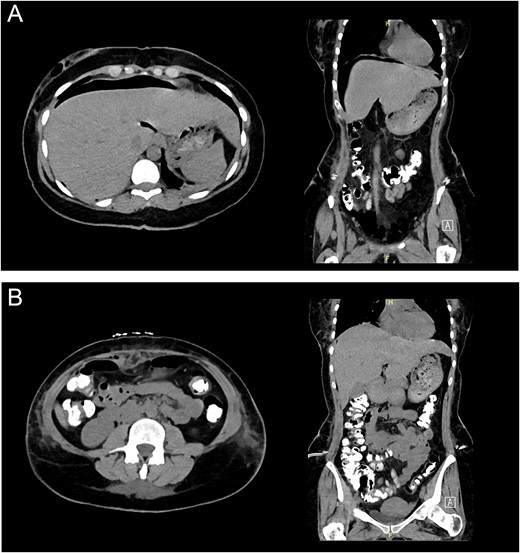

The general surgery team was consulted regarding the finding in chest X-ray film, and after assessment, an urgent abdominal computed tomography (CT) with intravenous, oral, and rectal contrast (Fig. 2A and B) was done showing a moderate amount of pneumoperitoneum as well as an extraperitoneal subcutaneous air foci was noted. However, the oral contrast is passing freely with no evidence of leak or extravasation.

(A) Abdominal CT demonstrating subphrenic pneumoperitoneum. (B) Abdominal CT with triple contrast without any contrast extravasation.